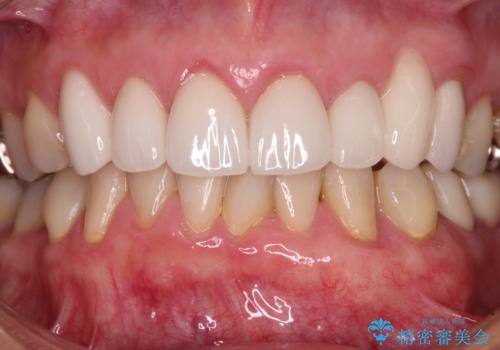

歯肉移植による根面被覆の結果、しみる症状は一切なくなりました。

歯肉の厚みが増したため、歯肉退縮のリスクが軽減されましたが、定期的に症状が再発していない確認していくことになります。